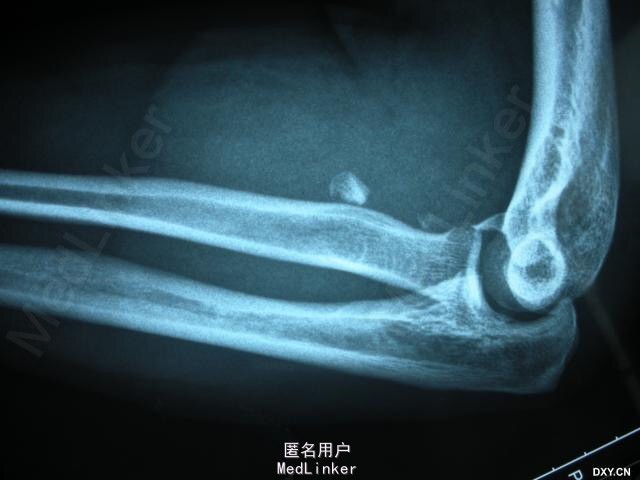

男,45岁,因高处跌落致左肘关节畸形、肿痛、活动障碍 3 天入院。伤后在外院行手法复位后来我院进一步诊治。体检:左肘关节肿胀明显,活动受限。无神经血管并发症。初步诊断:左肘关节损伤三联征。

术前X片